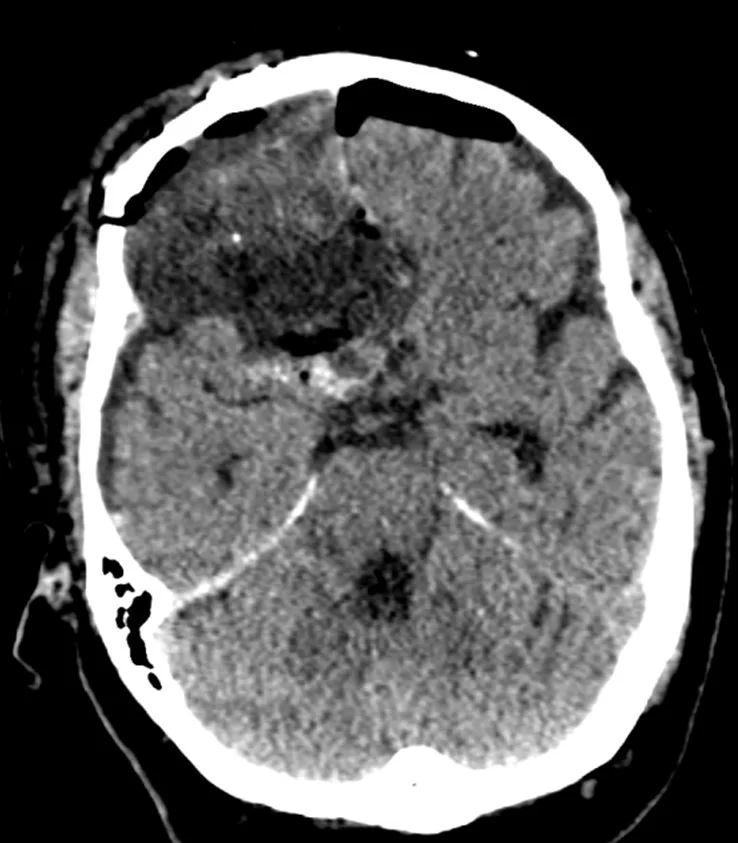

Ο απεικονιστικός έλεγχος με μαγνητική τομογραφία ανέδειξε ευμεγεθες οσφρητικό μηνιγγίωμα.

Διενεργήθη δεξιά υπερκόγχιος κρανιοτομία (τομή στο φρύδι) και ολική εξαίρεση της βλάβης.

Η ιστολογική εξέταση ανέδειξε μηνιγγίωμα WHO I.

Τρία χρόνια μετά, ο ασθενής παραμένει ελεύθερος υποτροπής και ασυμπτωματικός.